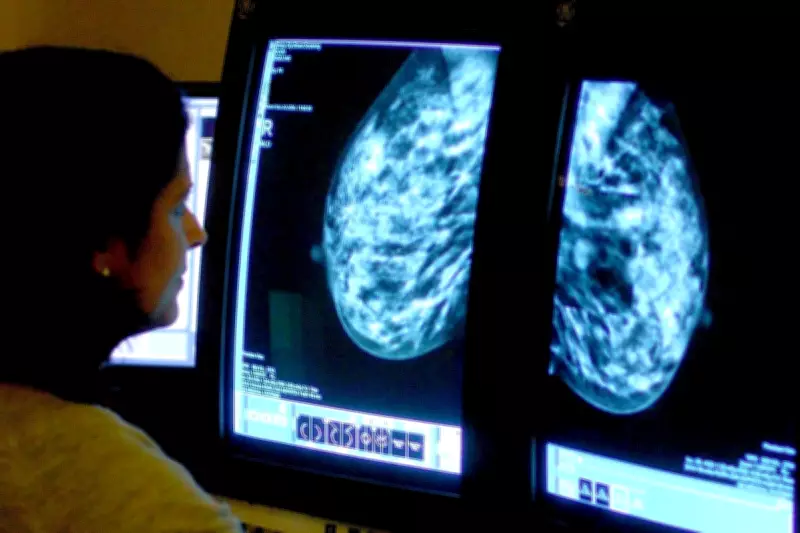

Current NHS breast cancer screening protocols require two specialist radiologists to examine each mammogram, a process that creates substantial workload pressures and can result in women waiting weeks for their results. The Swedish trial, involving 100,000 participants over two years, has shown that AI-supported screening could safely reduce this requirement to just one specialist while simultaneously improving detection accuracy.

The AI system underwent extensive training with over 200,000 examinations from institutions across more than ten countries before being deployed in the Swedish trial. It functioned by analysing mammograms and triaging cases according to risk level, with low-risk cases directed to single reading and high-risk cases to double reading by radiologists, while also highlighting suspicious findings for specialist attention.